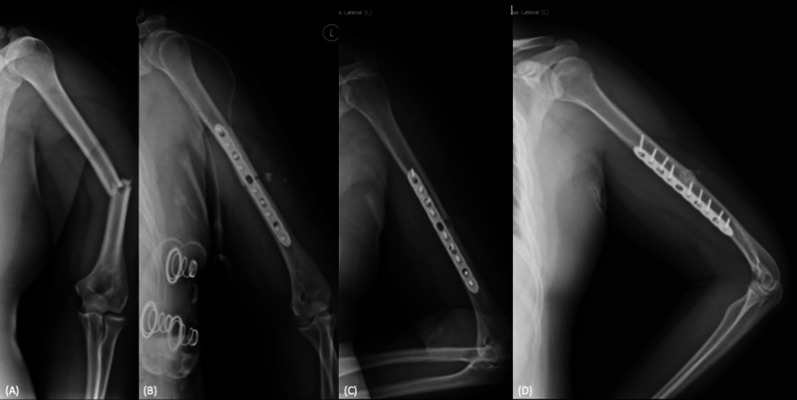

背景:肱骨骨干骨折(HDFs)术后延迟愈合的危险因素尚不清楚。因此,本研究旨在评估一组接受切开复位钢板固定(ORPF)治疗急性HDFs患者的放射学结果和延迟愈合相关的危险因素。材料和方法:2017年至2020年期间,采用标准压缩技术连续接受ORPF的AO/OTA 12-A和AO/OTA 12-B骨折患者纳入研究。收集了人口统计数据以及一系列医疗记录和x射线照片。纳入的患者分为及时愈合组(术后6个月内愈合)和延迟愈合组(术后6 ~ 12个月愈合)。检查各组之间的差异,随后应用逻辑回归进行危险因素分析。结果:纳入病例65例,男34例,女31例,中位年龄38.9岁。其中及时愈合组45例(69.2%),延迟愈合组20例(30.8%)。总体而言,30例(46.2%)表现为继发性骨愈合。在骨折类型、术后即刻骨折间隙、愈合模式和并发症发生率方面,组间观察到显著差异(p)。结论:在急性hsf的ORPF治疗中,尽管使用标准压迫技术,65例患者中有30例出现继发性骨愈合。骨折段间螺钉的应用可显著降低延迟愈合的风险。相反,术后并发症的出现与延迟愈合的可能性增加有关。所有程序均经作者所在医院机构审查委员会批准(IRB号:A-ER-112-395和IRB20230089)。

Background: The risk factors related to delayed union in humeral diaphyseal fractures (HDFs) following surgical osteosynthesis remain unclear. Therefore, this study aimed to evaluate radiological outcomes and the risk factors associated with delayed union in a retrospective cohort of patients who underwent open reduction and plate fixation (ORPF) for acute HDFs.

Materials and methods: Consecutive patients with AO/OTA 12-A and AO/OTA 12-B fractures who underwent ORPF using standard compression techniques between 2017 and 2020 were enrolled in the study. Demographic data, along with serial medical records and radiographs, were collected. The included patients were divided into two groups: the timely union (union occurring within 6 months postoperatively) and the delayed union group (union occurring between 6 and 12 months postoperatively). Differences between the groups were examined, and logistic regression was subsequently applied for risk factor analysis.

Results: Sixty-five cases were included in the study, consisting of 34 males and 31 females, with a median age of 38.9 years. Among these, 45 cases (69.2%) were classified in the timely union group, while 20 cases (30.8%) were classified in the delayed union group. Overall, 30 cases (46.2%) demonstrated secondary bony union. Significant differences were observed between groups in terms of fracture pattern, immediate postoperative fracture gap, union pattern, and complication rate (p < 0.05 for all comparisons). Multivariate logistic regression analysis revealed that the use of interfragmentary screw and the presence of postoperative complications were independent predictors of delayed union, with an adjusted odds ratio of 0.14 and 5.76, respectively.

Conclusions: In ORPF for acute HSFs, 30 out of 65 cases demonstrated secondary bone union despite the use of standard compression techniques. The application of interfragmentary screws significantly reduces the risk of delayed union. Conversely, the presence of postoperative complications is associated with an increased likelihood of delayed union.